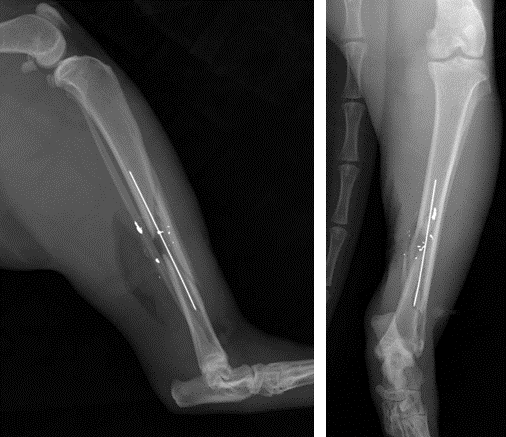

Des radiographies du membre ont été réalisées et montrent une fracture ouverte complexe diaphysaire comminutive du tibia gauche avec esquille et trait de refend et 2 plombs. La fibula est intacte (figure 1). Selon le système de classification de Gustilo [3], la fracture est une fracture ouverte de type II.

Fracture ouverte diaphysaire comminutive du tibia gauche avec 2 plombs

Figure 1 : Fracture ouverte diaphysaire comminutive du tibia gauche avec 2 plombs